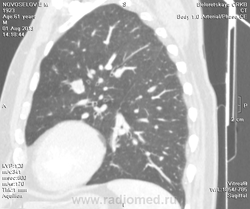

Мужчина оперирован по поводу BL щитовидной железы.Неоднократно проходил КТ в других лечебных учреждениях, у нас- впервые.Ставились заключения:MTS в лёгкие и лимф.узлы средостения слева.Образование слева увеличилось.Жалуется на одышку, не верит в заключение о MTS,просит узнать мнение других специалистов.

Метастазов в легкие не вижу. Похоже на лимфоузел в головке левого корня. Если позволите, запаздываете с началом исследования, плотность контраста в легочных артериях должна быть выше, чем а аорте. А одышка, не мудрено, легочная ткань диффузно уплотнена по типу "матового стекла", написал бы какую-нибудь интестициальную пневмонию, по типу альвеолита, может быть и гиперчуствительный пневмонит (не разберу есть или нет внутридольковые очажки), посмотреть бы изначально легочное окно, а не восстановленное из мягкотканного.

Кажется,я понял,что Вы имели ввиду.Очажки стрелочкой указал.Согласен с тем,что очаги на фоне отображеничя сосудов кажутся фантазией,но они присутствуют.

Коллега, вынужден извинться и дезавуировать свой первый пост. Пересмотрел. Да, есть очаги, и они - вероятнее всего, метастазы.

Единственное,что напрягает,так это то,что эти изменения у пациента более 1,5 лет.А вид внешний у него не так уж и плох.А слева это всё-таки лимфоузел, а не периферическое образование в S3?

Думаю, да. Слишком близко лежит к легочной артерии.